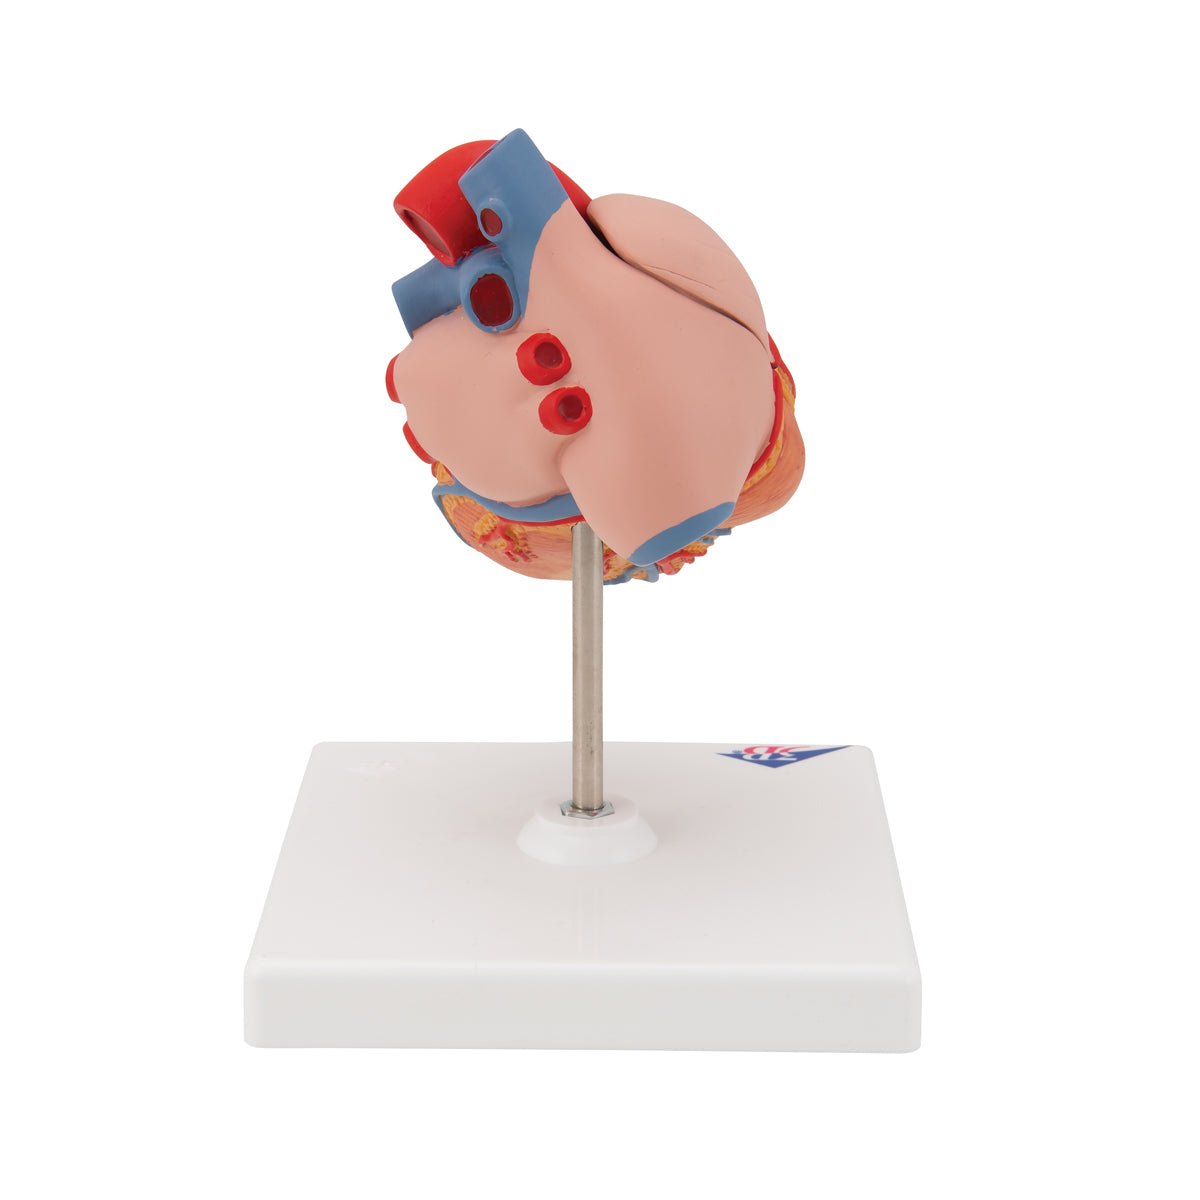

Anatomical models

Selling anatomical models is the mainstay of eAnatomi, although we also spend a lot of resources developing our own anatomical materials such as posters. Anatomical models are used for various purposes and can show both defined tissues, organs and organ systems. Are you looking for a simple model of bone tissue or perhaps an advanced torso model based on MRI technology, you can find it all at eanatomi.com.